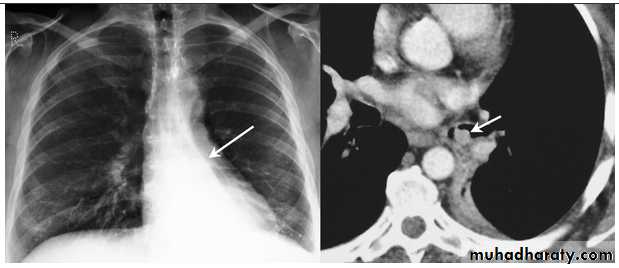

Thymoma.

A chest x-ray (A) reveals an unusual contour over the left hilum (arrows). That the hilum is not obscured (no silhouette sign) indicates that the mass must either be in front of or behind the hilum. A computed tomography scan (B) reveals a soft tissue mass (arrow) just to the left of the aorta. This is the most common location of a thymoma.Mediastinal teratoma. A chest x-ray (A) shows a large upper right mediastinal mass (arrows), but no specific internal structure is apparent. A computed tomography scan (B) reveals that the mass contains multiple types of tissue elements including fat (dark), soft tissue (gray), and calcium (white). This is essentially diagnostic of a teratoma.